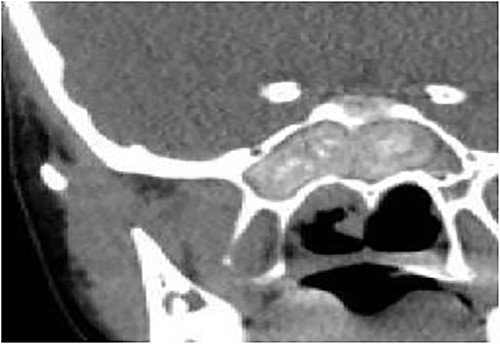

Case 3 (bilateral)

A 14-year-old male presented with a history of bilateral nasal obstruction for 3 years associated with snoring and postnasal discharge. Endoscopic examination showed bilateral nasal polyposis. CT scan of the paranasal sinuses (Fig. 3) & FESS, via which the sinuses were found full of polyps, mucin and fungal debris, confirmed the diagnosis of bilateral AFS. The patient continued on postoperative medical treatment and remained symptoms-free for 2 years follow-up.

Axial CT paranasal sinuses shows heterogeneous opacities filling the ethmoid and sphenoid sinuses bilaterally with hyperdense contents. The ethmoid sinus shows expansion with partial dehiscence of the right lamina papyracea.